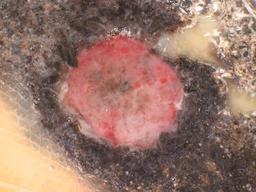

BRAAFF-Annotated Acral Lesions Dataset (BALD)

The BRAAFF-Annotated Acral Lesions Dataset (BALD): A curated set of dermatoscopic images of acral melanoma and nevi from various sources.

Müller C, Tschandl P, Rinner C, Kyrgidis A, Koga H, Moscarella E, Apalla Z, Di Stefani A, Kobayashi K, Lazaridou E, Longo C, Phan A, Saida T, Sotiriou E, Tanaka M, Thomas L, Zalaudek I, Argenziano G, Lallas A, Kittler H. The BRAAFF-Annotated Acral Lesions Dataset (BALD): A Curated Set of Dermatoscopic Images of Acral Melanoma and Nevi from Various Sources. J Invest Dermatol. 2025 Jan 17:S0022-202X(25)00021-1